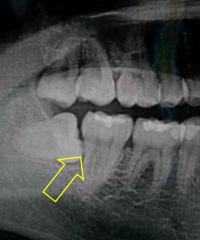

左上奥歯が割れています。一般的なレントゲンではわかりません。

CTでは破折線がはっきり見えます。患者様も納得しやすいです。